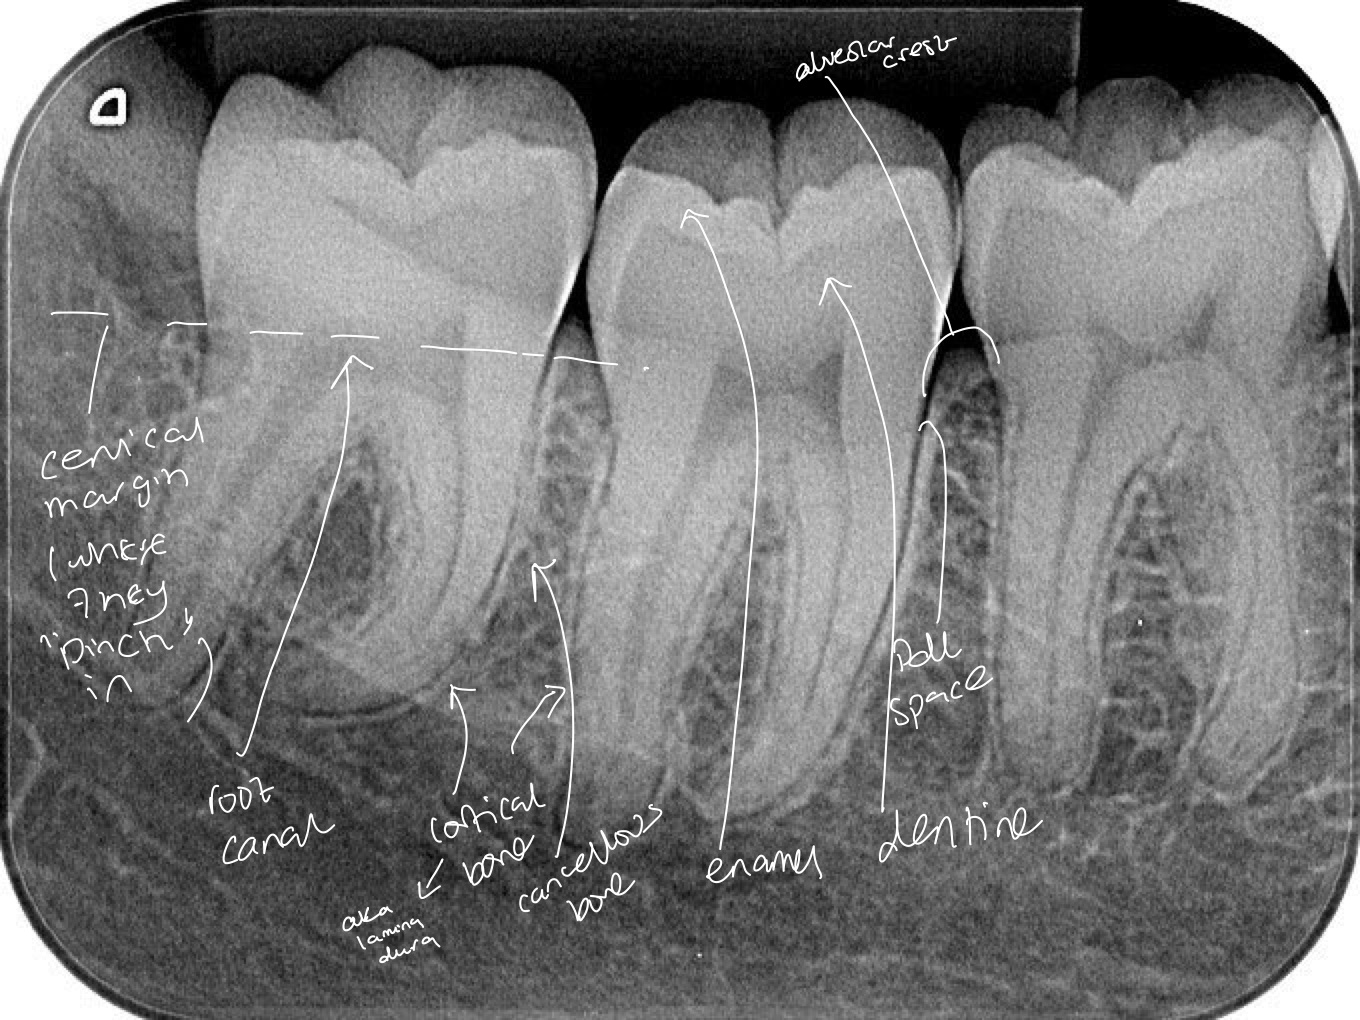

Dentine is of a lower density than enamel

Teeth sit in the alveolar bone, are separated from the bone by pdl

Lower right(mandible) quadrant- molars

High density enamel- radiopaque and white around the outside

Slightly lower density dentine-smooth grey

Root canal- soft tissue compared to enamel- doesn’t attenuate x rays as much- hence radiolucent(black) appearance

Black outline around tooth is the pdl space and next to it is a white line which is the bone. This is cortical bone, which is more dense than the cancellous bone seen between the teeth